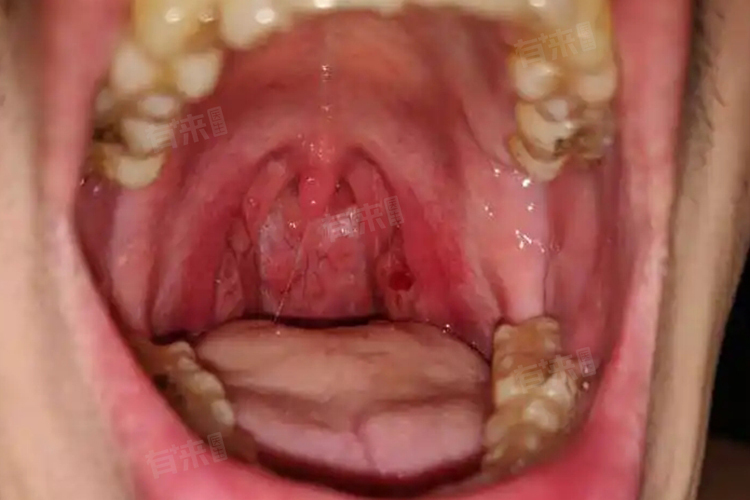

扁桃体切除手术是一种较为常见的外科手术,主要用于治疗反复发作的慢性扁桃体炎、扁桃体肥大等疾病。其费用因多种因素而有所不同,可能在5000-20000元不等。

- 传统的剥离法手术费用相对较低,一般在5000-8000元。这种手术方式是通过手术器械将扁桃体从周围组织中剥离并切除,手术创伤相对较大,术后恢复时间较长。

- 而低温等离子消融术是一种较为先进的技术,利用低温等离子射频能量对扁桃体组织进行消融切除,具有手术创伤小、出血少、恢复快等优点,但其费用相对较高,一般在8000-15000元。